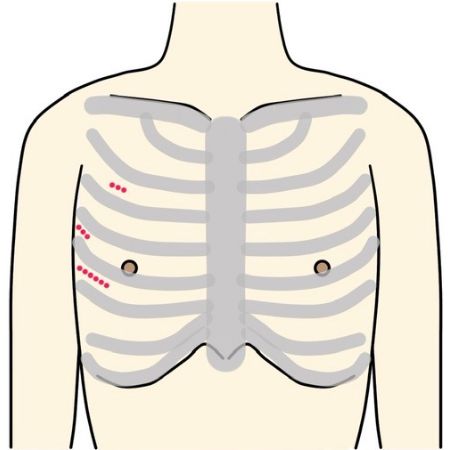

“体に対する負担が少ない手術”です

Minimally Invasive Cardiac Surgeryの略で、心臓低侵襲手術のことを意味します。

従来であれば胸骨という胸の真ん中を約20cm程切開しますが、MICSでは肋骨の間を3〜5cm程切開して行います。

当院では可能な方には3D内視鏡を用いた完全内視鏡下手術、及び傷が正面から目立ちにくい脇の下からの方法で、どちらも骨を切らず治療を行なっております。

- ※画像の無断転用は禁止です